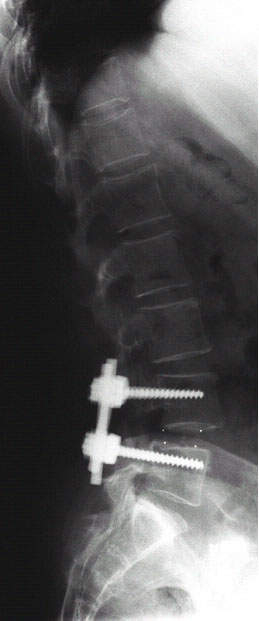

Abb.4-6

Seitliche Röntgenaufnahmen der selben Patientin nach der Operation (links) und nach einem Jahr (rechts). In jeden Wirbelkörper sind zwei Titanschrauben eingebracht (Bild mitte), verbunden sind die Schrauben mit jeweils zwei Titanstangen. Als Ersatz für die entfernte Bandscheibe dienen zwei Kunststoffwürfel (aus Carbon, erkennbar an punktförmigen Röntgenmarkierungen), welche mit dem Knochen des Patienten gefüllt sind. Auf dem rechten Bild ist die knöcherne Verbindung beider Wirbelkörper erkennbar.